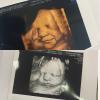

Самые лучшие фотки получились на 3 скрининге, 31 неделя

Лицо видно четко ❤️

Я ходила на 27 неделе, так как врач сказал, что самый оптимальный срок, и действительно, фотографии отличные вышли

На 33 неделе ходила, тоже фото отличное вышло

В 37 ходила, там одни щеки)

Но тоже получилось нормально